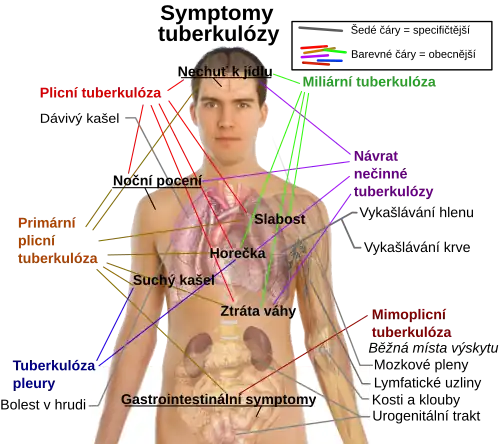

Nejtypičtějším příznakem je chronický kašel s krvavým sputem – vykašlávání nebo chrlení krve (hemoptoe nebo také hemoptýza), horečka (Febris), noční pocení a ztráta tělesné hmotnosti. Infekce dalších orgánů způsobuje velkou škálu symptomů. Diagnóza se provádí mikrobiologickým vyšetřením sputa či odebraných vzorků tkáně, tuberkulinovým testem, pomocí radiologie (nejčastěji rentgenem hrudi) nebo krevními testy. Léčba je náročná a vyžaduje dlouhodobé užívání různých antibiotik. Vzrůstajícím problémem při léčbě je antibiotická rezistence některých druhů tuberkulózy. Prevence spočívá ve screeningu a očkování, převážně bacilem Calmettovým-Guérinovým (BCG) – očkování proti tuberkulóze se označuje jako kalmetizace.

Klinické příznaky a symptomy

Poté, co onemocnění přejde do aktivního stadia, v 75 % případů zahrnuje infekci plic (plicní tuberkulóza). Mezi symptomy patří bolest hrudi, vykašlávání krve a kašel trvající déle než tři týdny, horečka, třesavka, noční pocení, ztráta chuti k jídlu, ztráta tělesné hmotnosti, pobledlost a únava.[113]

Ve zbylých 25 % případů se infekce přesune z plic a způsobuje jiné formy tuberkulózy, kterým se hromadně říká mimoplicní tuberkulóza.[114] To častěji probíhá u lidí s potlačenou imunitou a u malých dětí. Při tuberkulóze mízních uzlin (krtice) uzliny natékají a později z nich může začít vytékat tekutina. Tuberkulóza kostí a kloubů způsobuje bolest a oslabení kostí, které jsou pak náchylnější na zlomeniny. Může postihovat prakticky všechny kosti, např. obratle (Pottova nemoc) nebo čelistní kosti – z nich nejčastěji lícní kost, do které se šíří hematogenně (přenos krevní cestou) nebo per continuitatem (přestupem skrz tkáně), a projevy jsou charakteristické vznikem píštělí a vtažených jizev. Symptomy tuberkulózy trávicí soustavy jsou bolest břicha, průjem a krvácení z řitního otvoru. Urogenitální tuberkulóza způsobuje např. bolest při močení a krvavou moč a tuberkulóza centrální nervové soustavy způsobuje mimo jiné bolest hlavy, zamlžené vidění a záchvaty.[113] Dále existuje např. tuberkulóza kůže (lupus vulgaris nebo tuberculosis verrucosa cutis) způsobující pupínky, bradavice, puchýře nebo vředy[115] nebo tuberkulóza osrdečníku způsobující těžkosti při dýchání a bolest hrudi.[116] Obzvláště nebezpečnou formou tuberkulózy je miliární tuberkulóza, která napadá několik míst zároveň. Mimoplicní a plicní tuberkulóza mohou probíhat současně.[89]